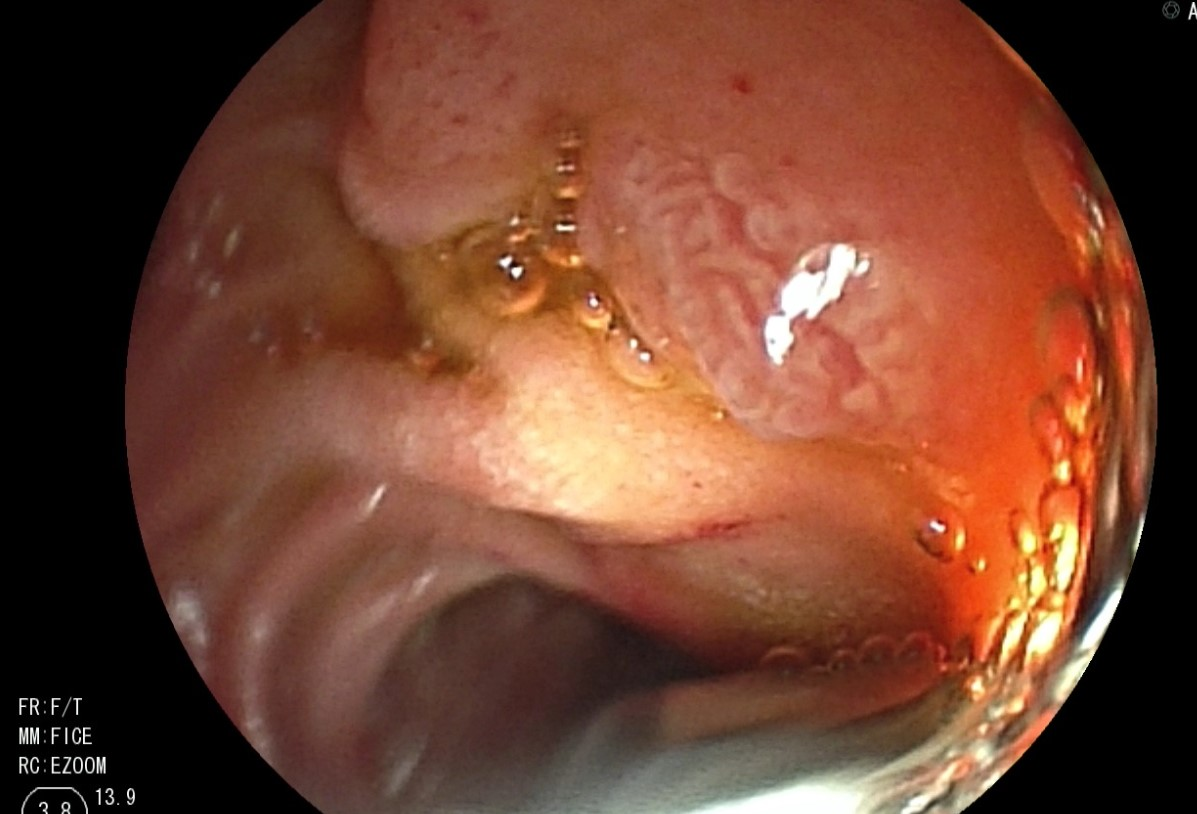

行腹部CT扫描后,初步鉴别诊断包括恶性肿瘤(如胰腺癌或神经内分泌肿瘤)、急性胰腺炎所致实质炎症、胰腺囊肿或胰腺动静脉畸形(arteriovenous malformation,AVM)。内镜检查时,可见少量血液从乳头部流出(即胰管

诊断结果:胰腺AVM所致急性胰腺炎。